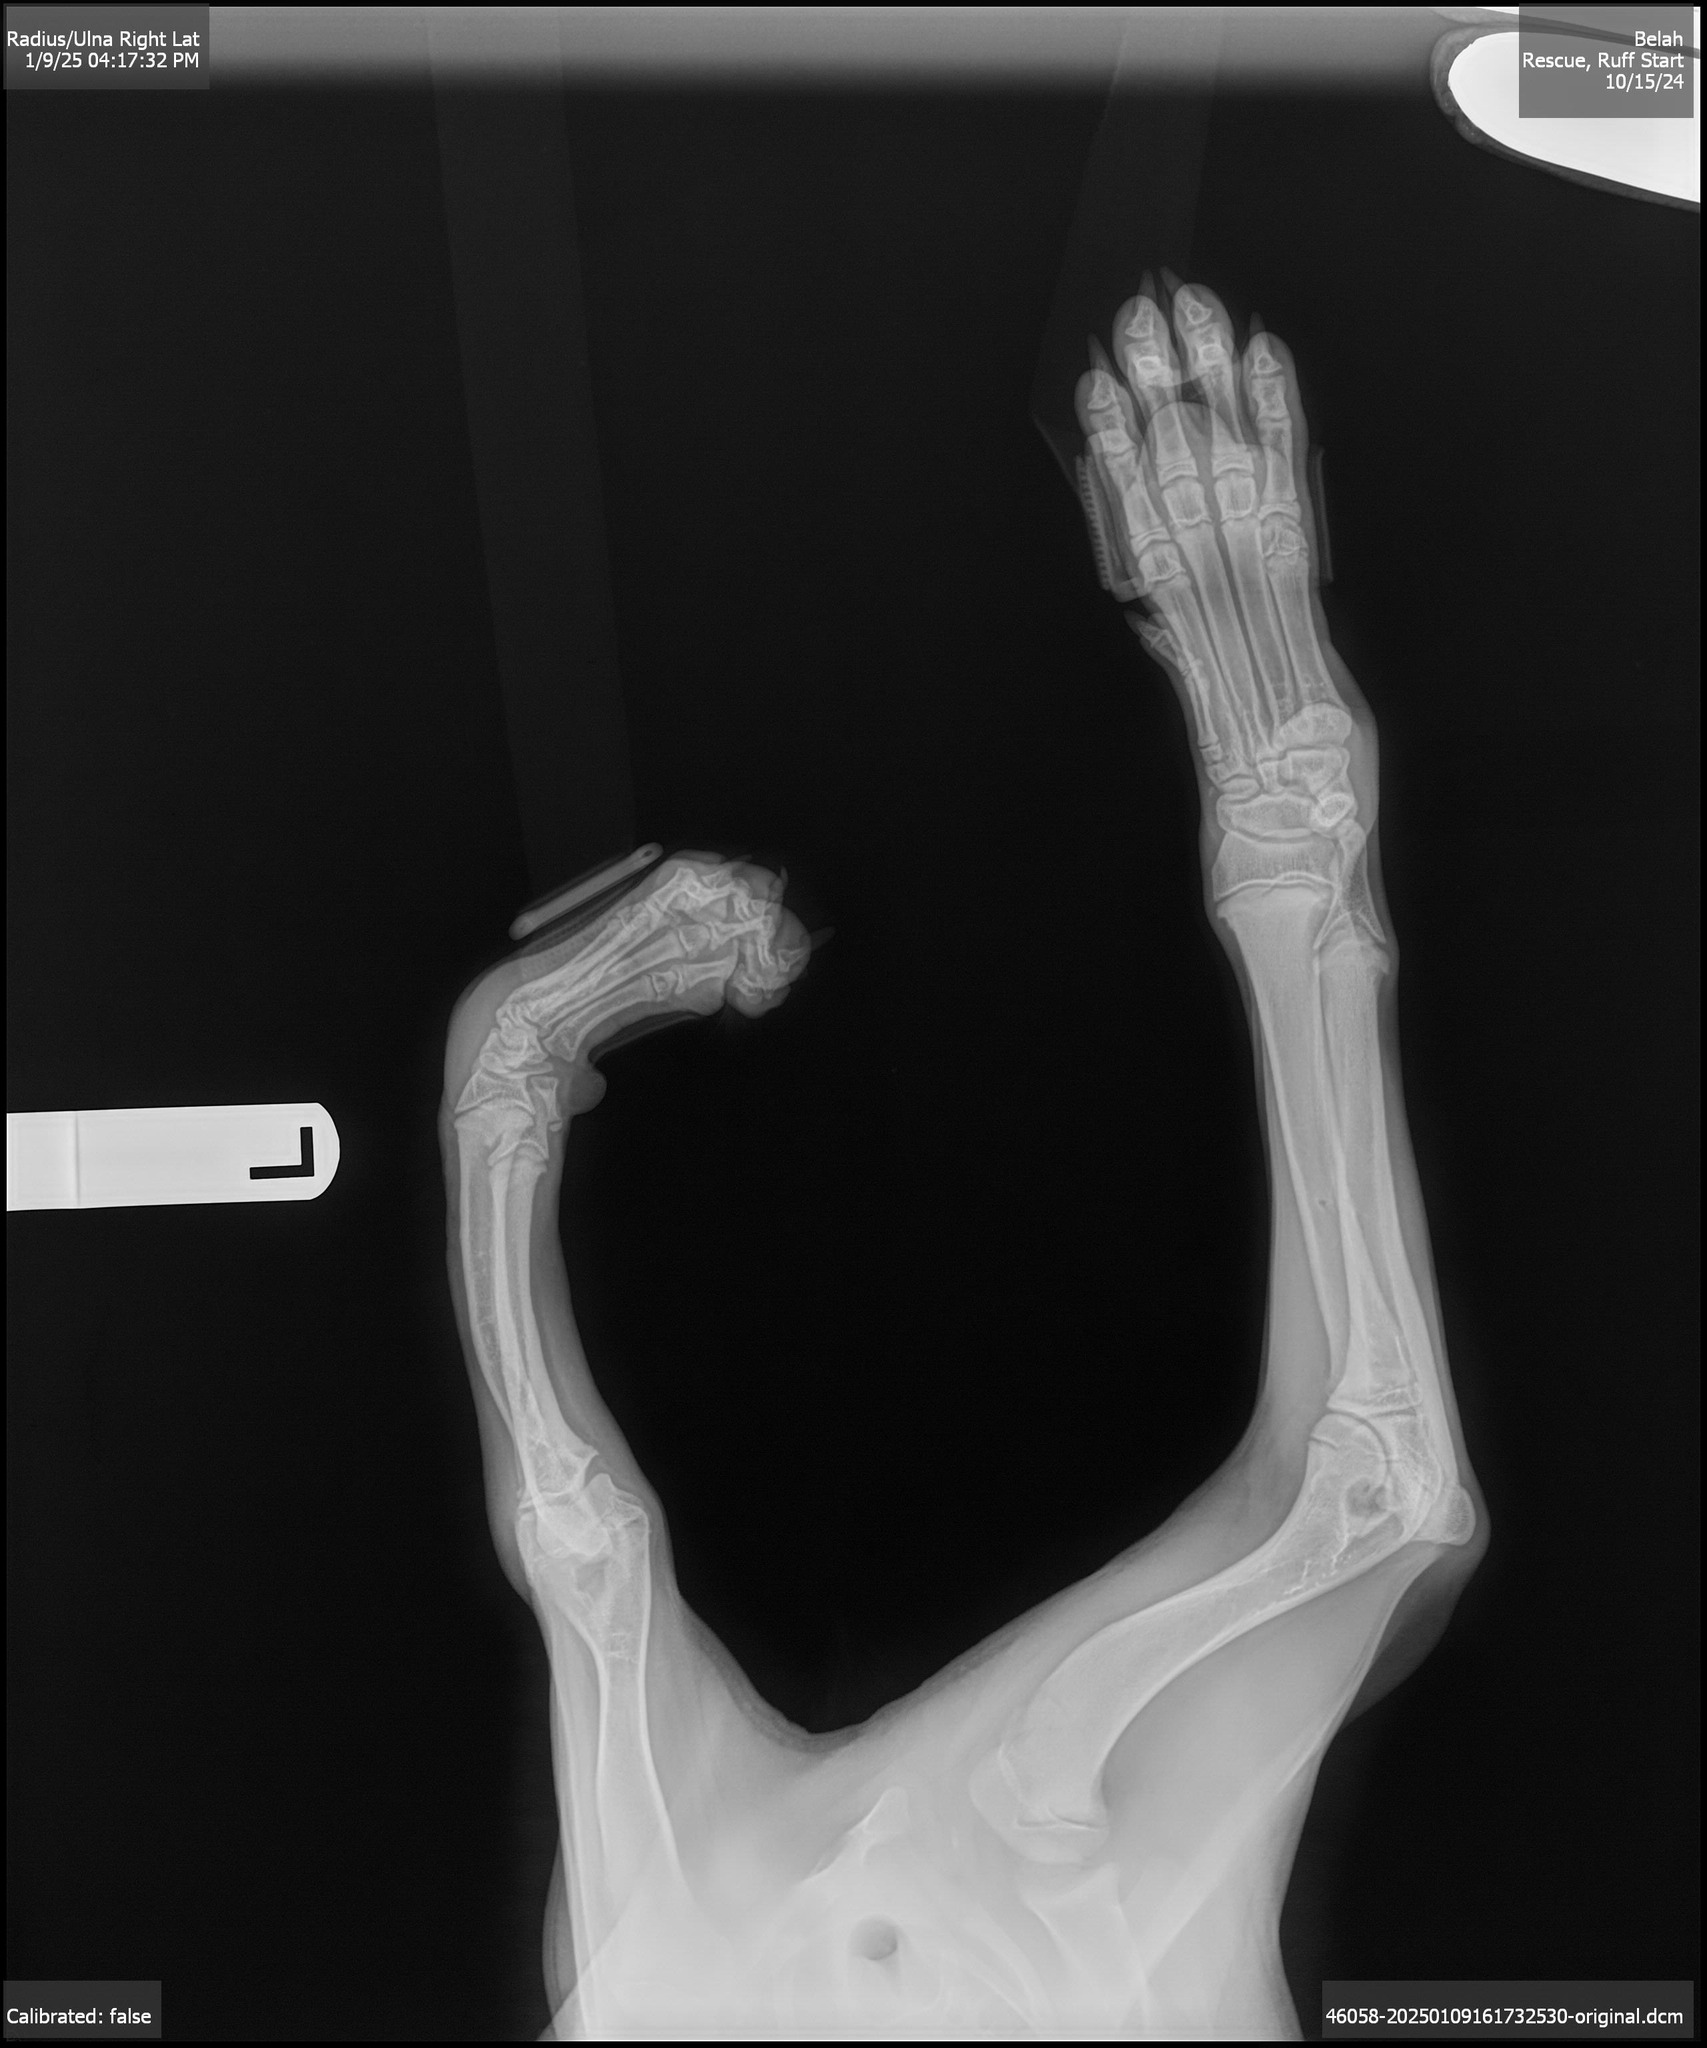

we learned that she has severe angular limb deformity in her left front leg and carpal hyperextension in her right front leg. Likely caused by birth defects or a past injury, her condition isn’t painful, but it does cause some instability.